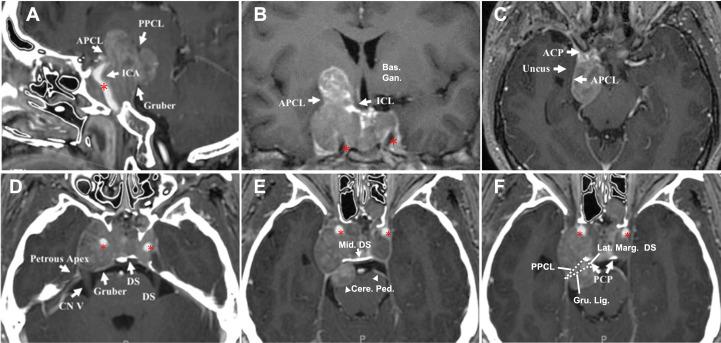

To understand the different characteristics and growth corridors of knosp grade 4 pituitary adenomas (Knosp4PA) with cavernous sinus (CS) compartments penetration and intracranial extension, aiming to improve the safety, effectiveness, and total resection rate of surgery.

A case series of 120 Knosp4PA patients with 187 invaded compartments were retrospectively reviewed. A novel surgery-relevant grading system was proposed according to the CS penetrating features. The details of approach drafting, risk prediction, and complication avoidance were analyzed and integrated through illustrated cases.

All enrolled tumor was Knosp4PA which was derived from Knosp subgrades 3A(62.5%) and 3B(37.5%). Based on the tumor growth pathway and its relevant features, five subclassifications of intracranial extension(n=98,81.7%) were classified, which derived from the superior (Dolenc's and Oculomotor subtype, 5% and 24.2%), lateral (Parkinson's subtype,18.3%), and posterior (cerebral peduncle and Dorello's subtype, 5.8% and 1.7%) CS compartment penetration. The size of intracranial extension is assessed by Lou's scale proposed here based on preoperative MRI characteristics. Under Lou's scale, the gross total rate (GTR) decreased (82%, 53%, 22%, and 19%) with grades increased (grade 0,1,2,3, respectively), and presents significant difference between the four groups (p=0.000), as well as between single and multiple compartments involved (p=0.001). Preoperative cranial nerve deficits included the optic nerve (53%), oculomotor nerve (24.2%), and abducent nerve (4.2%), with an overall rate of visual function improvement in 68.1%. Postoperative complications of transient diabetes insipidus, cerebrospinal fluid (CSF) leakage, and cranial nerve deficits were 6.7%, 0.8%, and 0%. No new cranial nerve deficits occurred. The mortality rate was 0.8%.

The concept of "penetration" refines the extracavernous growth pattern, and the five intracranial subclassifications help to understand the potential extension corridors, enhancing adequate exposure and targeted resection of Knosp4PA. This grading system may benefit from its predictive and prognostic value, from which a higher GTR rate can be achieved.